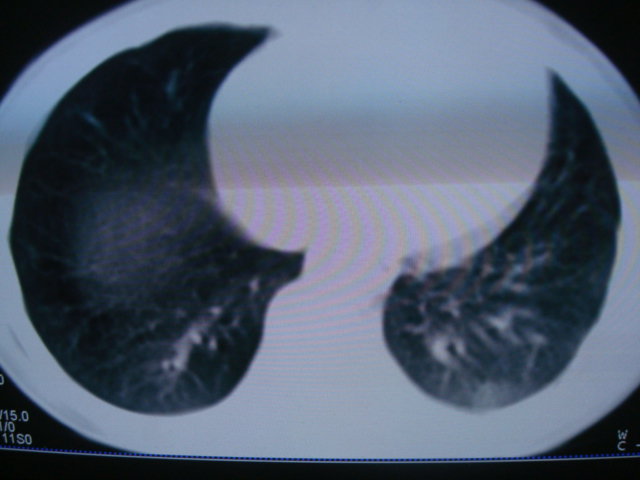

标题: PED0869:男,10岁,肺内多发结节+胸水 [打印本页]

标题: PED0869:男,10岁,肺内多发结节+胸水

男,10岁,左胸痛,发热轻,血象高。后到省级权威医院治疗,病情明显好转,结果几天后公布。老机器,图像质量差,见谅。

考虑血源性肺脓肿或韦氏肉芽肿

考虑血源性肺脓肿

血源性肺脓肿可能。